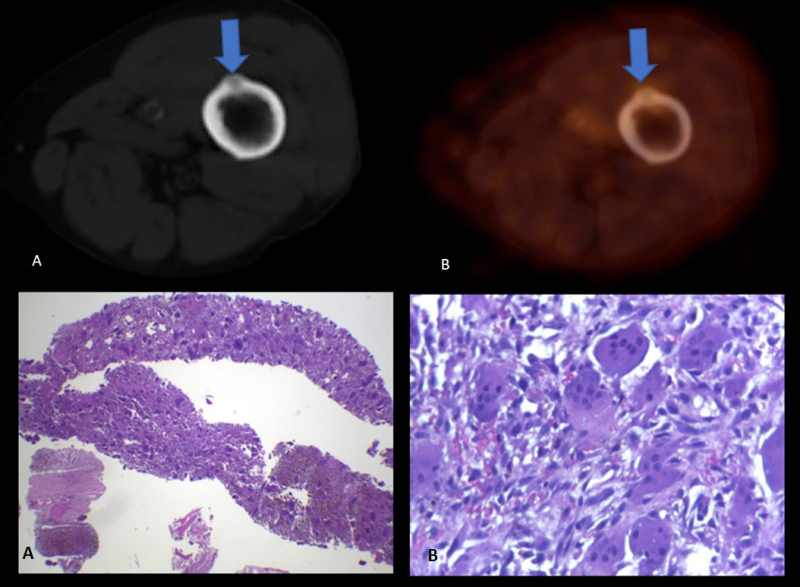

Paciente de 72 años con insuficiencia renal crónica en plan de trasplante, con cirugía previa de paratiroides. Por valores elevados persistentes de PTH y ante resultados confusos del centellograma con 99m Tc- sestamibi, se realiza PET-CT con 18F-Colina para detectar presencia de tejido paratiroideo hiperfuncionante. En el estudio híbrido morfo-molecular se evidencia imagen nodular de 17 mm en región ínfero medial cervical anterior con aumento de la captación del radiotrazador (SUV máx. 3,5) consistente con tejido paratiroideo (fig. 3). Además, se detecta una lesión predominantemente lítica e hipercaptante de 26 mm de diámetro en la espina del omóplato izquierdo, que cursaba en forma asintomática (fig. 4, arriba). Se realiza biopsia de la misma, dando como resultado tumor pardo (fig. 4, abajo).